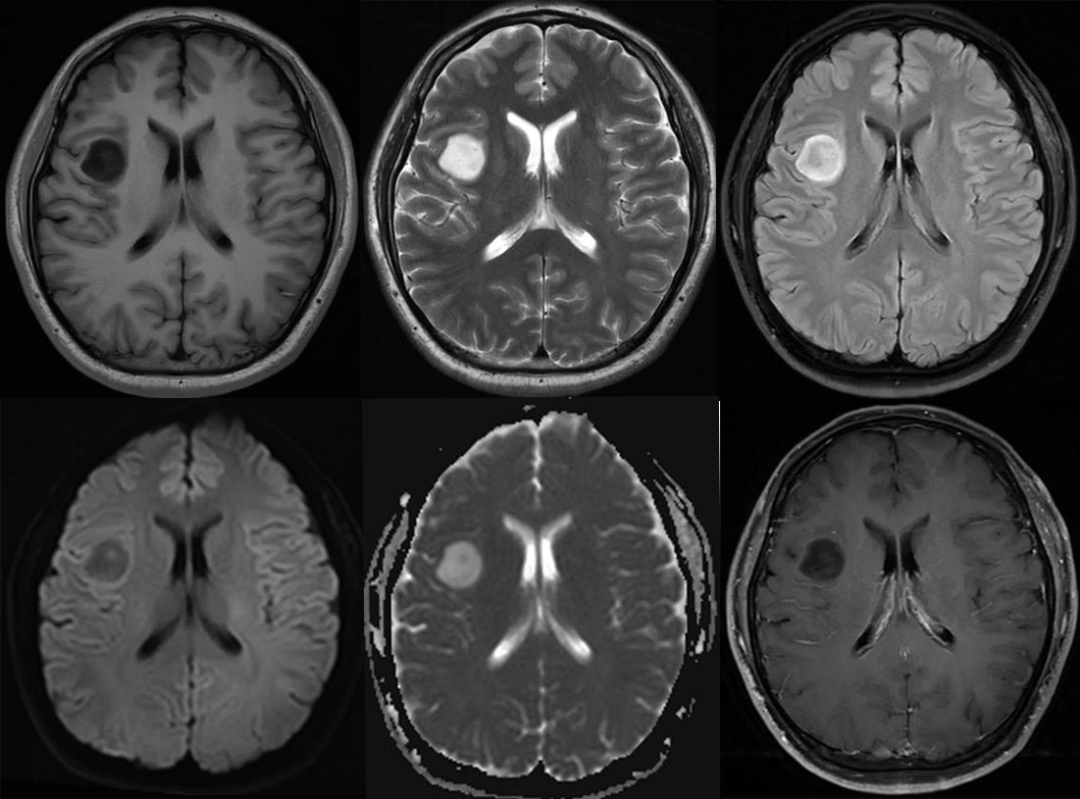

T2-FLAIR 错配征——这个影像征象很特异